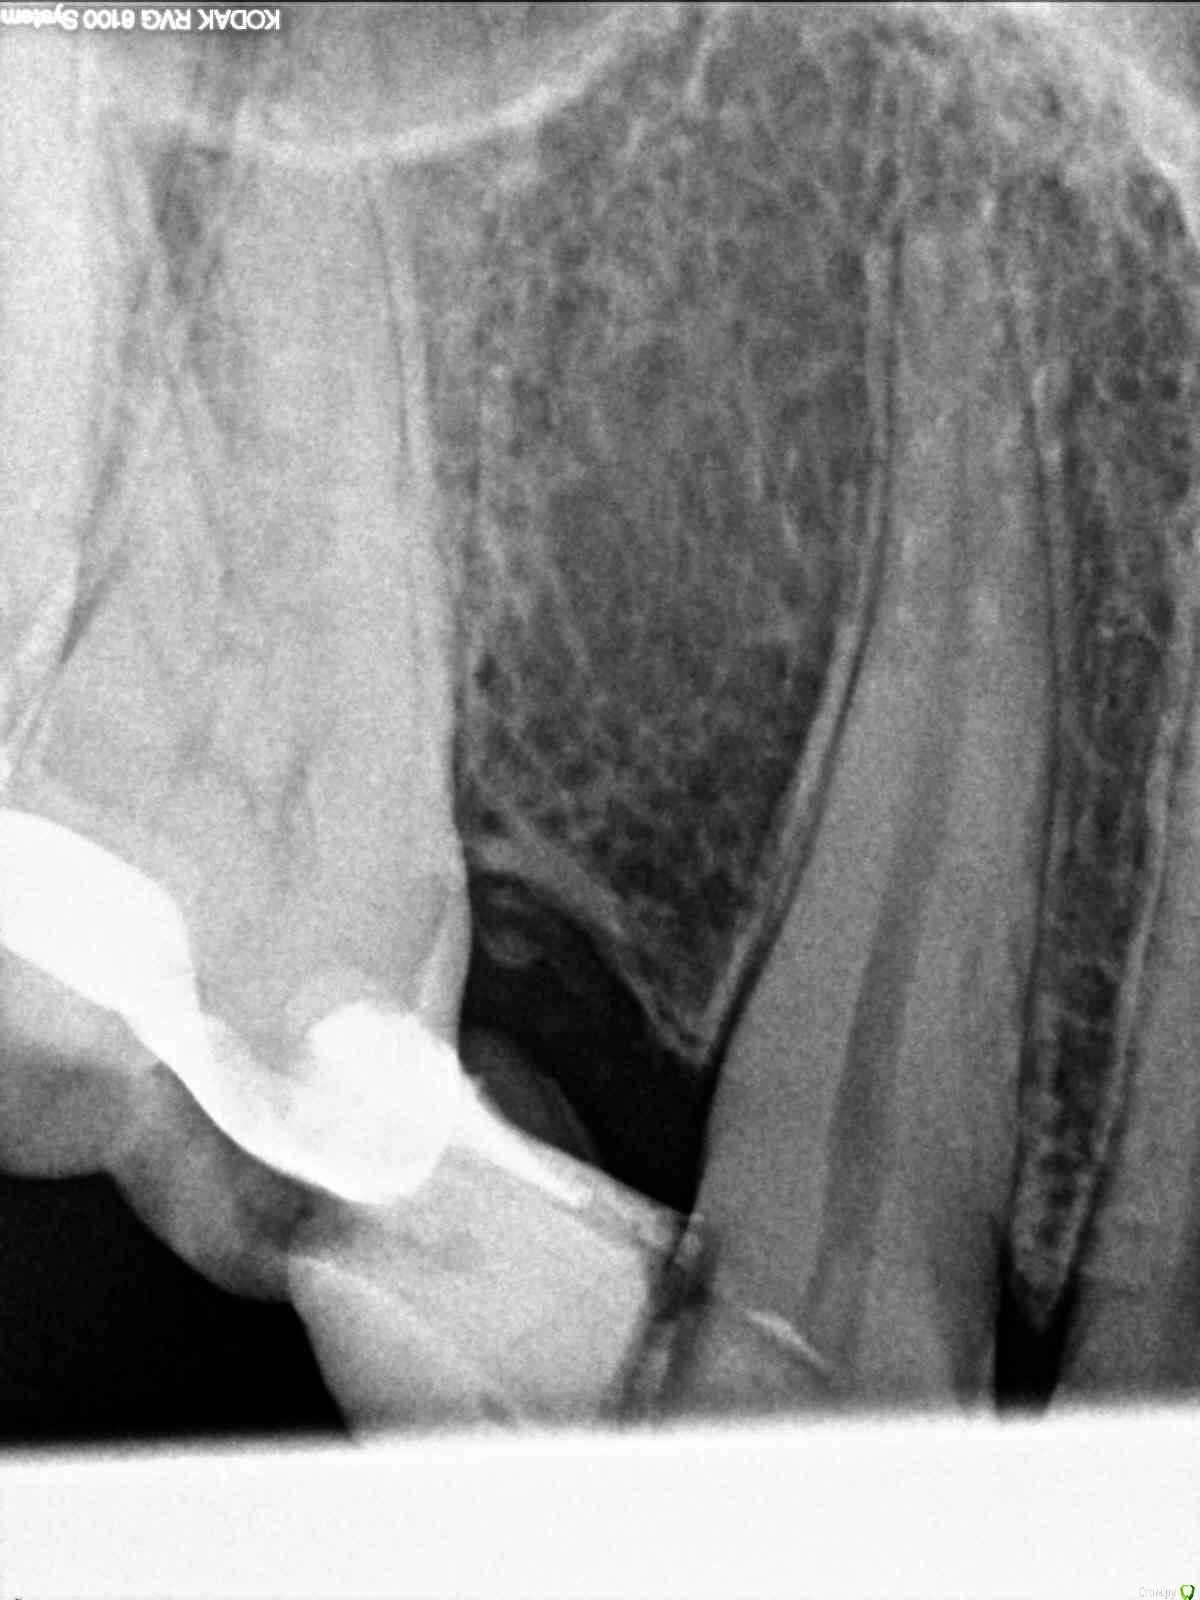

milina Опубликовано 9 декабря, 2016 Поделиться Опубликовано 9 декабря, 2016 (изменено) Здравствуйте! Очень нужна ваша помощь. Обратилась в стоматологию по поводу несильной ноющей боли в 6 верхнем зубе и стало больно надкусывать этим зубом. Два первых снимка сделаны за 2 недели до этого. На зубе крепится мерилендовсий протез, поставленный много лет назад. Стоматолог удалил нерв, он был по ее словам уже погибшим, белого цвета. 3 канала прочистили, заложили пасту с кальцием.После прохождения действия анестезии, стал очень болеть зуб, даже при касании его языком, чувство распирания, кусать вообще невозможно было. На след. день я обратилась в клинику, другой доктор снял временную пломбу, промыл каналы и отправил домой полоскать содой и солью. Стало легче, но меня еще беспокоила боль при пальпации слизистой в районе верхушки корня. Еще на следующий день мой стоматолог посмотрела, сказала, что возможно у меня реакция на пасту, при прочистке каналов болезненность была только в одном из них на верхушке. Заложила пасту с гвоздичным маслом и поставила временную пломбу. Боль стала потихоньку снижаться на следующий день и появился постоянный привкус этого масла во рту. Через три дня снова посетила стоматолога, промыли опять каналы, по ее словам все чисто, ни гноя, ни сукровицы. Так же присутствовала болезненность в одном канале. Заложила какое-то лекарство, стало сразу очень больно, промыли, заложили другое лекарство, к сожалению, не спросила, какое именно. Врачу я сообщила, что присутствует боль при пальпации над корнем и появилось под слизистой небольшое уплотнение, миллиметра два. При внешнем осмотре ничего не видно. Сделали снимок, качество ужасное, но врач сказала, что ничего там плохого не видит., на мой взгляд, на нем вообще ничего не видно, еще и накладывается гайморова пазуха. После приема стала чувствовать боль в зубе при ходьбе, когда топаешь ногой, или при похлопывании по голове, все отдается в зубе. Прошло два дня, сильных болей нет, но зуб чувствую постоянно, при надкусывании болезненность, присутствует чувство распирания, терпимая боль при пальпации слизистой в районе корня и так же присутствует уплотнение под слизистой. Помимо этого сегодня обнаружила, что со стороны больного зуба увеличились лимфоузлы под ухом и под нижней челюстью.Температура сейчас в районе 37, такая же была и до лечения 37-37.3. Уважаемые доктора, как вы считаете, положительная динамика присутствует или состояние ухудшается и мне нужно обратиться к другому специалисту. Меня волнуют эта шишечка под слизистой и лимфоузлы. Как бы хуже не стало. Изменено 9 декабря, 2016 пользователем milina Ссылка на комментарий